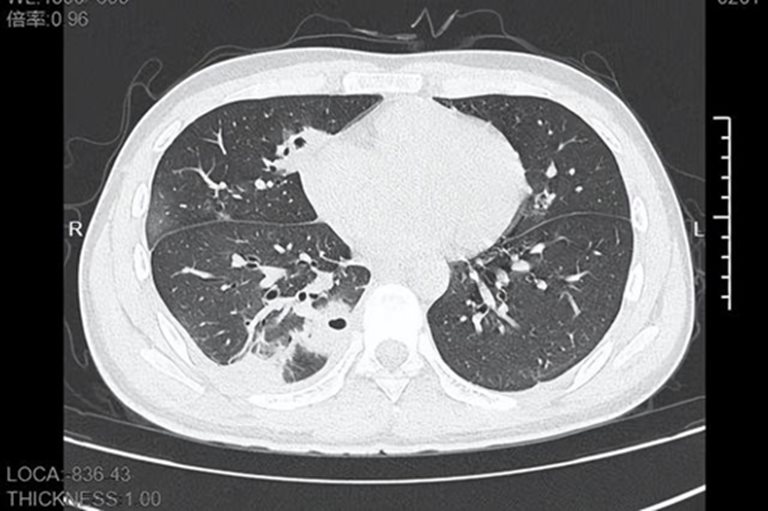

ในที่สุดจางได้ตัดสินไปโรงพยาบาล ขณะที่ไปถึง เขามีไข้สูงถึง 39 องศาเซลเซียส แพทย์ได้ทำ CT scan ทรวงอก ผลปรากฏว่าพบรู หรือที่เรียกว่า โพรงในปอด (pulmonary cavities) ซึ่งเป็นช่องว่างผิดปกติภายในเนื้อเยื่อปอดมากกว่า 10 โพรง เนื้อเยื่อปอดบางส่วนมีเนื้อตายและมีหนองสะสมอยู่ภายใน

แพทย์วินิจฉัยว่าผู้ป่วยมีอาการของฝีในปอด (Lung abscess) ที่เกิดจากการติดเชื้อแบคทีเรียในกระแสเลือด โดยผลการตรวจทดสอบแสดงให้เห็นว่า เกิดจากเชื้อแบคทีเรียชนิด Staphylococcus aureus ซึ่งเป็นแบคทีเรียที่อาศัยอยู่บนผิวหนังของคน ทำให้เกิดการติดเชื้อได้ตั้งแต่เล็กน้อยไปจนถึงรุนแรง ซึ่งภายหลังจากการสอบถามทำให้สามารถยืนยันได้ว่าต้นเหตุมาจาก "การบีบสิว"